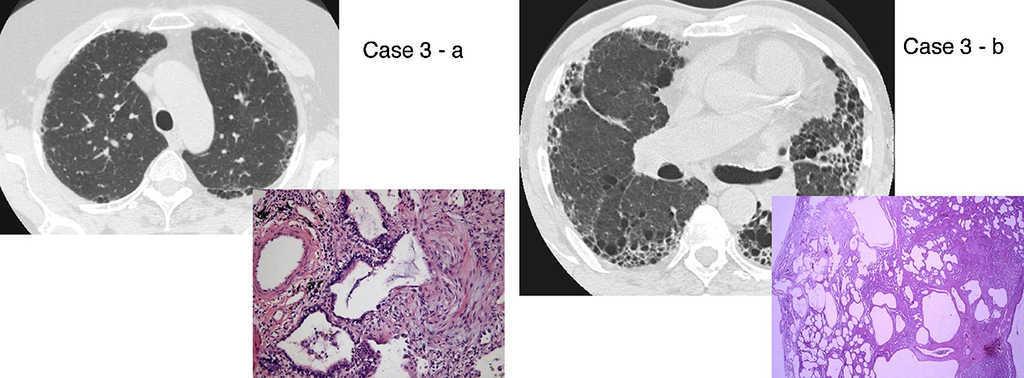

There are two aspects that may raise doubts in the HRTC interpretation: the distinction between honeycombing and traction bronchiolectasis and fibrosis with emphysema. The differential diagnosis is a challenge even for an experienced radiologist.47, 49, 50 The 2011 ATS/ERS/JRS/ALAT multidisciplinary consensus1 stated that the identification of four typical findings establishes the definite diagnosis of UIP: 1 – subpleural and basal lung lesions predominance; 2 – reticulation; 3 – honeycombing with/without traction bronchiectasis/bronchiolectasis; 4 – absence of findings that do not support a UIP pattern (Table 2, Table 3; Figure 2).

Figure 2. UIP/IPF identification in HRCT and histopathology. Case 1 – a: Common histopathological features of UIP/IPF consisting in honeycombing as a result of subpleural airway spaces confluence with bronchialization of epithelium where mucus cells may be predominant. HE 100×. Case 1 – b: The previous image aspects are revealed by higher production of mucus occupying the new formed subpleural smaller confluent airspaces. HE 100×. Case 1 – c: The interstitium intermingling honey-combing loses elastin fibres and is represented by fusiform cells, either fibroblasts or miofibroblasts, with collagen deposition. Elastin-van Gieson 100×. Case 2 – a: Irregular confluent air spaces with typical subpleural localization of UIP/IPF honeycombing with interstitium enlargement by fusiform cells. HE 100×. Case 2 – b: The adjacent lobular parenchyma accentuate histopathological heterogeneity, starting by overinflation and pseudo emphysema morphology. HE 100×. Case 2 – c: The lobular histopathological remodelling aspect of fibrosis enlarging alveoli septae till central bronchiolo-vascular axes and alveolar bronchialization. HE 100×. Case 3 – a: Small subpeural confluent air-spaces with bronchial-like epithelium and juvenile foci of fibroblasts in myxoid matrix; lymphocytes are seen. PAS 200×. Case 3 – b: UIP/IPF heterogeneous morphology in airspaces confluence with subpleural preponderance and committing the whole lobule. HE 100×.

The histological pattern of UIP must present: 1 – marked fibrosis/architectural distortion, with or without honeycombing in a predominantly subpleural/paraseptal distribution; 2 – patchy involvement of lung parenchyma by fibrosis; 3 – fibroblast foci; 4 – absence of features against a diagnosis of UIP suggesting an alternate diagnosis1, 51 (Figure 2).